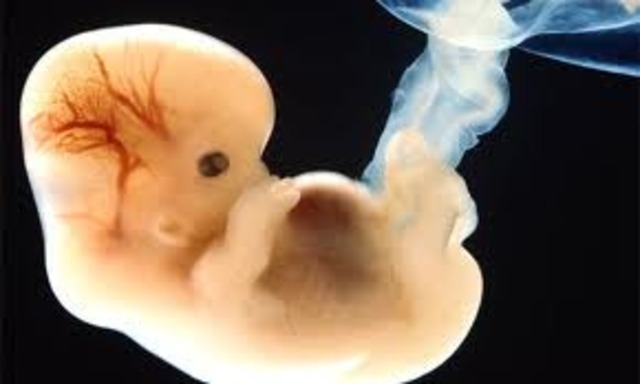

It is the differentiation and developmental stage. The cells will start to differentiate to special kind of tissues which will develop into major organs. At this stage the child will called embryo. Three types of tissues include ectoderm, endoderm and mesoderm. The names of those tissues are referring to their functions ecto means outer layer, endo means inner layer and meso means in between or sandwich layer and derm means tissue. The ectoderm will form most of the outer tissue and organs incl

2 weeks to 8 weeks